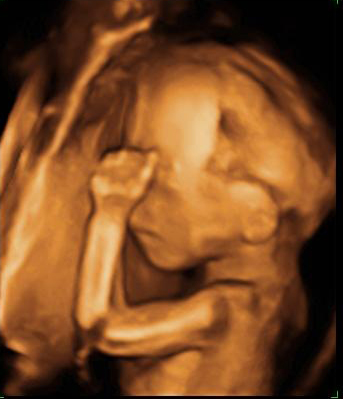

Ecografía 3D de la semana 20: Huesos craneales y del brazo

Esta imagen de una ecografía en 3D en la semana 20 de gestación al feto se le distinguen los huesos de los brazos y del cráneo, así como las fontanelas. Estas son aberturas en los huesos del cráneo que van a permitir que se superpongan cuando el bebé atraviese el canal del parto al nacer.

Bebé de espaldas mostrando el brazo

Si nos fijamos se nota la fontanela y los huesos craneales. También se ven de forma nítida los huesos del brazo: húmero, cúbito y radio.